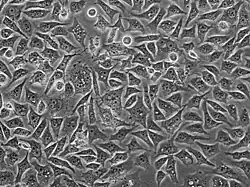

PC3 cell cultured in plastic plate